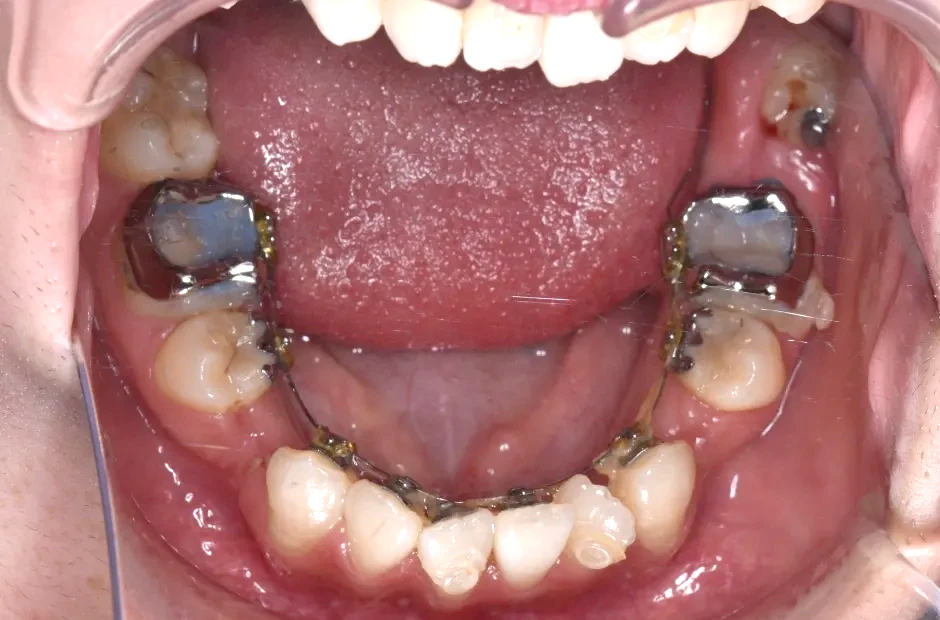

叢生

| 診断名・主訴 | 叢生 |

|---|---|

| 年齢・性別 | 43歳・女性 |

| 治療期間・回数 | 2年7か月 27回 |

| 治療に用いた主な装置 | 舌側矯正 |

| 抜歯部位 | 両顎4,4 |

| 治療費 | 100万円(税抜) |

| リスク・副作用 | 装置による違和感・疼痛・歯肉退縮・歯根吸収・虫歯のリスクなど |

治療前

治療中

治療後